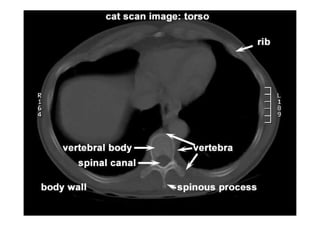

Referência: http://www.accessexcellence.org/RC/VL/

figura

Imagem na tela ou no filme

Convencionou-se examinar a TC

produzida como se estivesse

olhando para ela de baixo para

cima (a partir dos pés do

paciente), assim é importante

lembrar que as estruturas vistas

a sua direita são aquelas do lado

esquerdo do corpo do paciente.